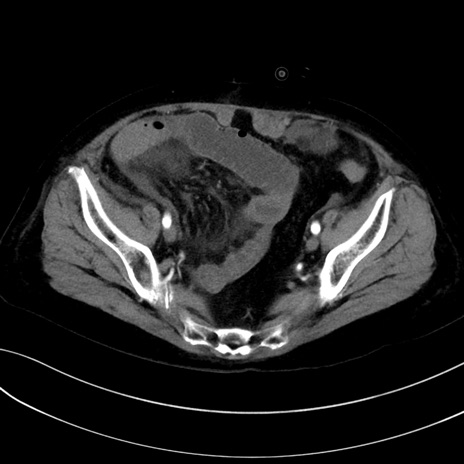

症例13 CT(横断像)1日半後